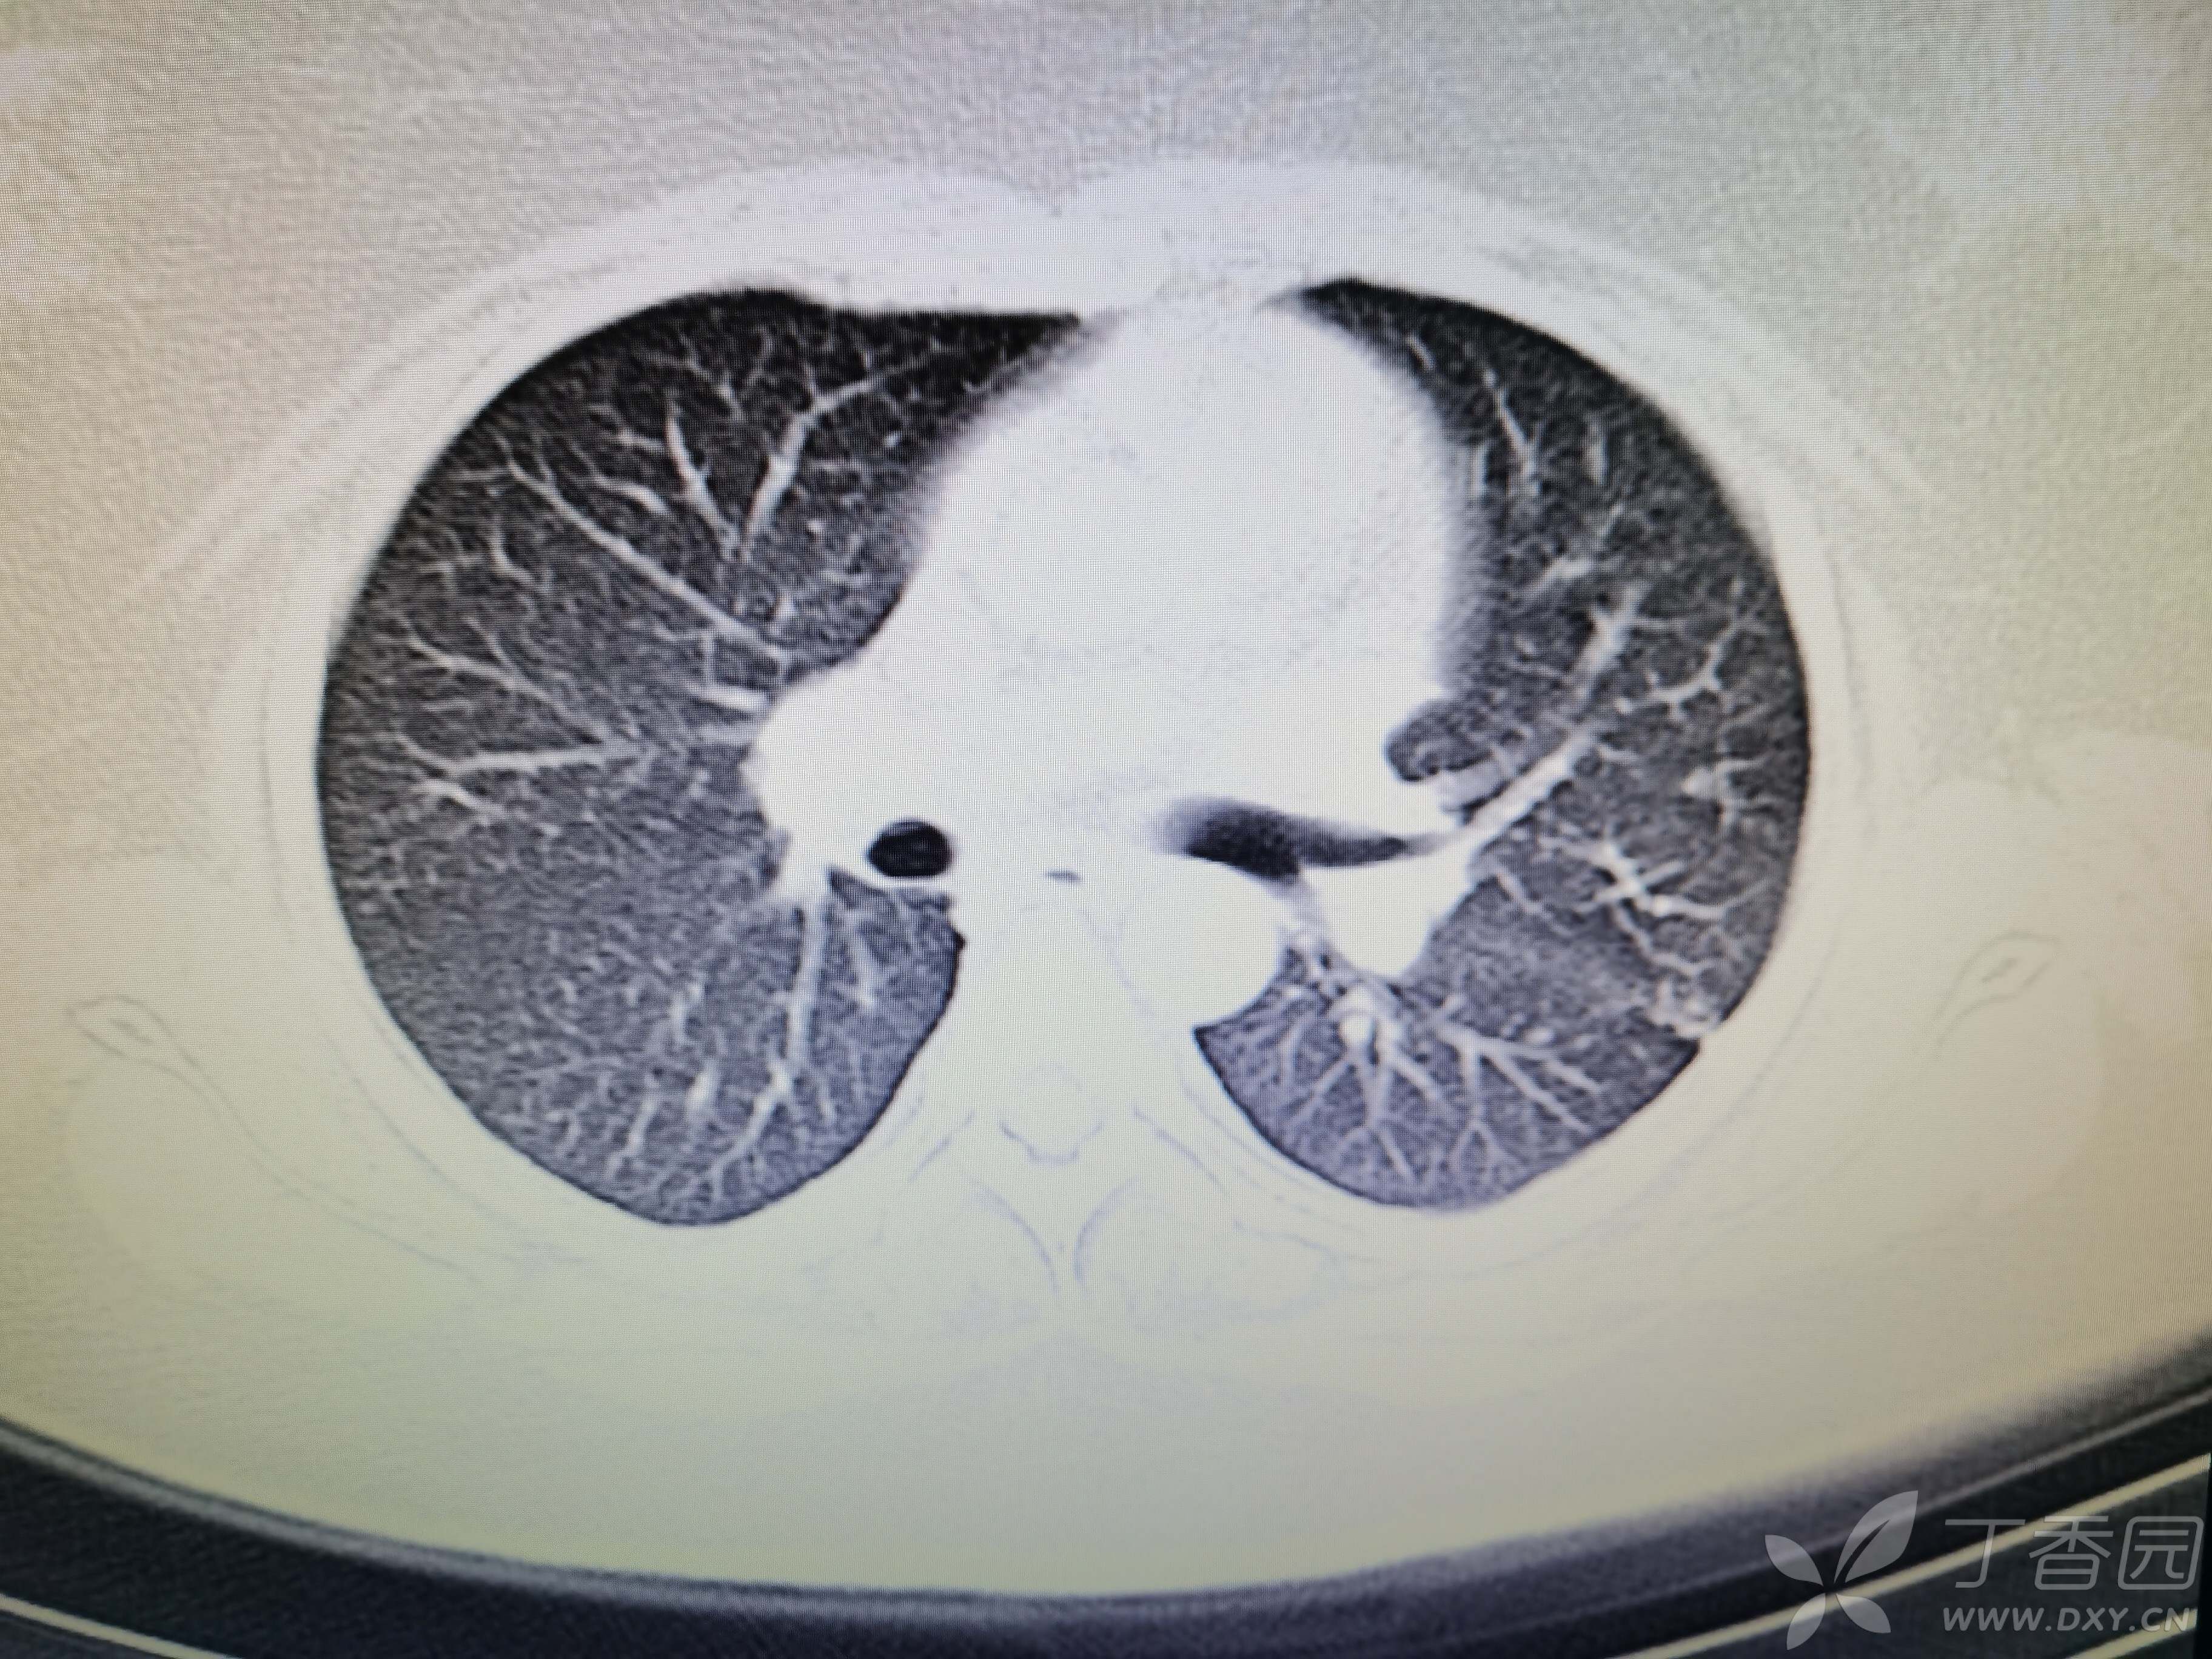

基本信息:女,三十几岁,印度人。。

胸部CT:

如题:猜肺部病灶病理。。